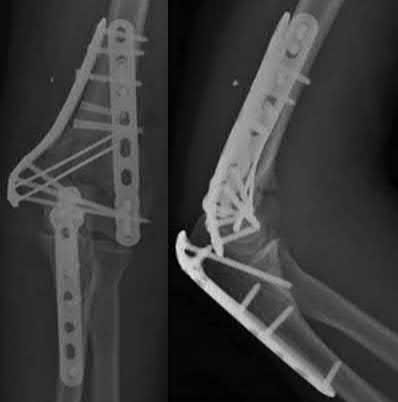

A 51-year-old carpenter presents with a distal humerus nonunion (Figures A and B). After repair of the nonunion, he is lost to follow up for 3 months and then presents to your clinic pain-free and with evidence of fracture union. On examination the elbow arc of motion is 10-80 degrees. Following a brief failed trial of conservative management, you recommend:

Limited flexion outside a functional range of motion (30-130 degrees) can be quite debilitating, and it is often addressed with open release of the posterior bundle of the MCL and posterior capsule and excision of osteophytes.

A frequent complication of distal humerus fractures is post-traumatic stiffness. This patient has had multiple procedures about the distal humerus, and the question stem implies that he did not complete a structured range of motion protocol following the repair of his nonunion. Beyond a trial of conservative management, there are many techniques described for capsule and soft tissue releases as well as bony resections if heterotopic ossification is present. This patient's severely limited flexion would best be addressed with a release of the posterior bundle of the MCL, and with flexion